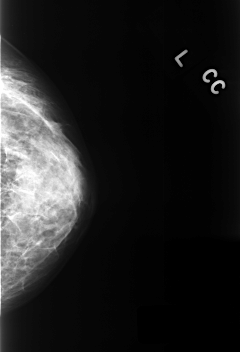

C_0327_1.LEFT_CC

LEFT_CC LINES 4224 PIXELS_PER_LINE 2880 BITS_PER_PIXEL 12 RESOLUTION 50 NON_OVERLAY